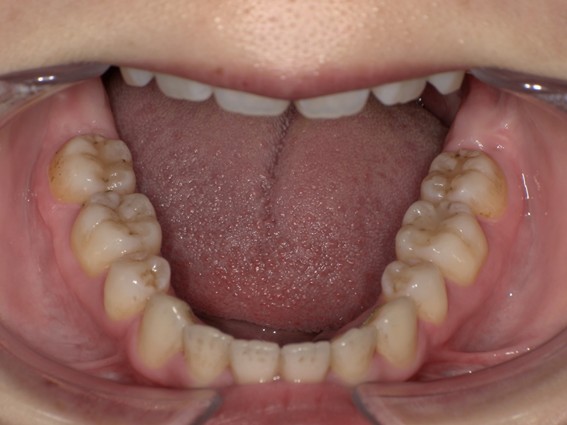

| 主訴 | 口元がでている、口が閉じずらい、上の歯と下の歯のがたつき、顎がない。 |

| 治療内容 | 上下のワイヤー矯正を行いました。 |

以前骨切りを勧められたことがあるという方でしたが、抜歯矯正で口元の突出や顎のしわを改善しました。上唇の厚みや頬の高さを考慮し、老けた印象にならないよう配慮。お顔全体のバランスと年齢に合わせた治療を行いました。